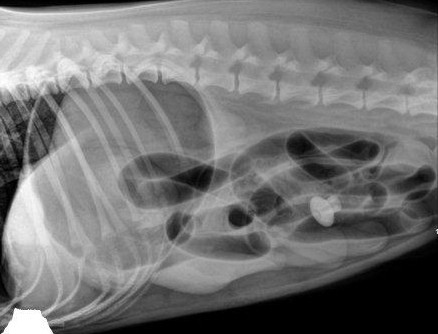

Определить непроходимость с точностью можно только на осмотре у врача. В ряде случаев для определения болезненного участка, особенно у худых животных, достаточно тщательной пальпации (прощупывания). Рентгеноконтрастные предметы могут быть определены на обычном обзорном рентгеновском снимке брюшной полости.

Зачастую поставить точный окончательный диагноз можно только проведя рентгеноконтрастное исследование. Это серия снимков, сделанная через определенные интервалы после выпаивания животному раствора сульфата бария. Контраст показывает скорость продвижения рентгеноконтрастный массы по кишечнику и обволакивает инородное тело, что также может способствовать его визуализации.